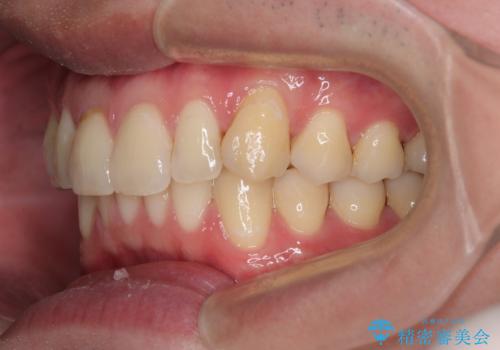

上下のデコボコを治したい インビザラインによる矯正治療

- 前歯のデコボコと突出感を気にして来院された患者様です。

極力目立たない装置を希望とのことで、インビザラインを用いて非抜歯で矯正治療を行うこととしました。

事前に親知らず4本を抜歯し、多少歯列を後方に移動できるように準備をした上で、なるべく歯と歯の間を削ることなくデコボコを解消できるように計画しました。

お仕事が忙しく、1日の装着時間は不十分となる日もありましたが、治療は順調に進めていくことができました。

途中、以前大きなむし歯で処置をした歯が痛み出し、根管治療が必要となったため、根管治療とオールセラミッククラウンによる補綴治療を行い、その後にインビザラインによる仕上げの歯列移動を行い、無事に治療を終えることができました。